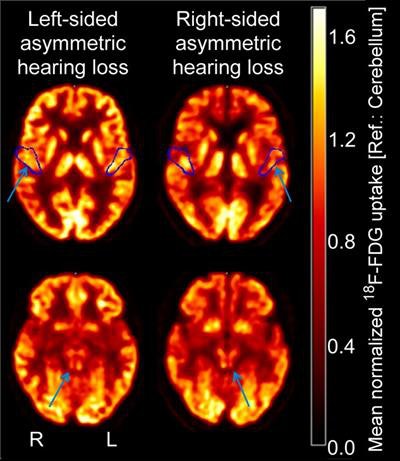

Researchers found that decreased FDG uptake occurred in the inferior colliculus and primary auditory cortex on the opposite side of the head to the ear with hearing loss. The ability to determine the severity of this imbalance could help direct otolaryngologists choose the best course of action for their patients.

The digital PET images revealed that significantly lower FDG uptake correlated with the side of the head that was opposite to the ear with the hearing deficiency. In other words, reduced uptake FDG in the left inferior colliculus or left primary auditory cortex was indicative of hearing loss in the right ear. This contralateral pattern was evident with the inferior colliculus in 11 patients (84.6%) and with the primary auditory cortex in 12 patients (92.3%).

In addition, a longer duration of hearing impairment was associated with a higher metabolism on the contralateral primary auditory cortex. By contrast, duration of hearing impairment did not predict regional glucose metabolism for the ipsilateral primary auditory cortex or either side of the inferior colliculus.